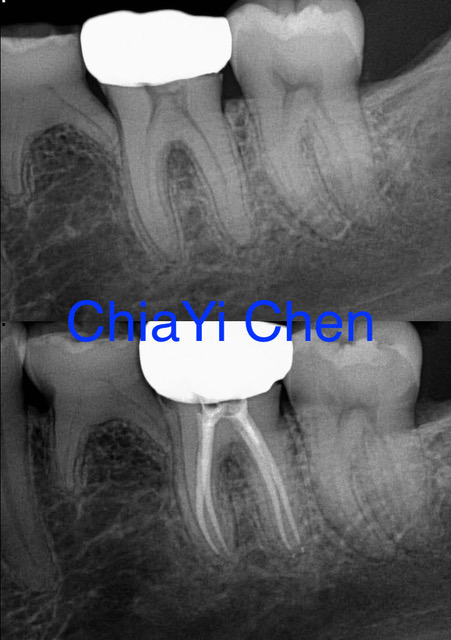

The Procedure of a Root Canal Treatment

To begin, our endodontist will start by numbing the area around the affected tooth using local anesthesia. This ensures that you feel little to no pain during the procedure. Once you are numb and comfortable, our endodontist will create a small access hole in the crown of your tooth. Through this access point, they will carefully remove any infected or damaged pulp from within the roots and chambers of your tooth. This helps eliminate any infection and prevents further damage to surrounding tissues.

After cleaning out all traces of infection, our endodontist will then shape and sterilize the canals before filling them with a rubber-like material called gutta-percha. This material provides stability and prevents reinfection.

In some cases where there is extensive damage or an increased risk of fracture, a dental crown may be recommended for added protection. Our endodontist will take impressions of your teeth to create a customized crown that perfectly fits over your treated tooth.